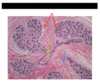

What does the green arrow point at?

Terminal duct

What does the blue arrow point to?

Interlobar connective tissue

What do the red arrows point to?

Lobules